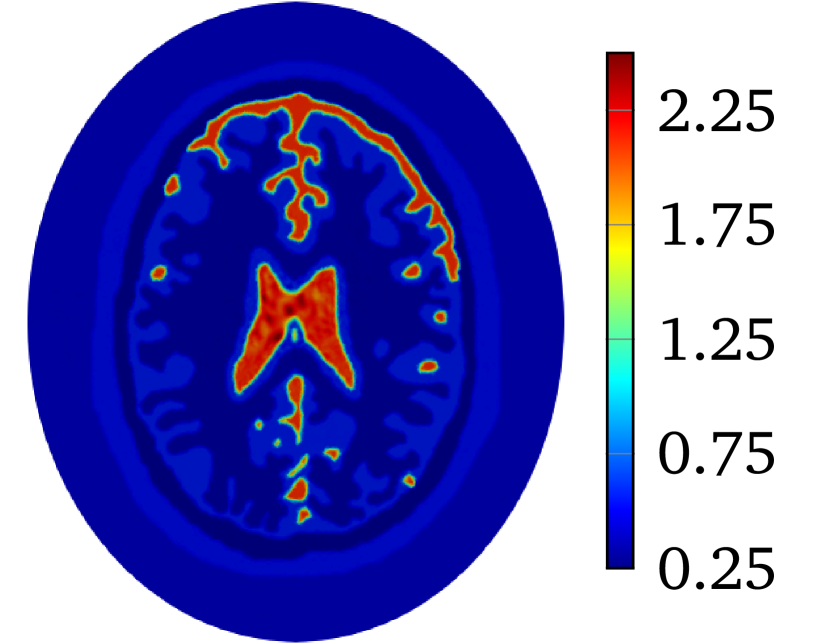

to produce with for 2D problem. The constant is selected so that . The value of is and for heart-lung model and human-brain model, respectively. The true smoothed distributions of for the two models are shown in Figure 2.

The LM-SCEM algorithm is used to reconstruct the distribution of . The initial guess is given as which is the value of the background tissue. The conductivity in the region for is supposed to be known. The values of are truncated to only update for with . The discontinuity caused by this truncation can be removed by applying (20) properly (either by mollification or simply by replacing the discontinuous values), but it does not cause any numerical problems since is small, so no special treatment was done in the following computation. The values of for the first 15 iterations are shown in Figure 4(a). The relative error is also given in Figure 4(b). With noise, the reconstruction with uniformly converges to with 15 iterations. The reconstructed is shown in Figure 5(a). To achieve a level of , it takes more than 40 iterations. A reconstruction with and is then carried out, but a similar speed of convergence and relative error is observed, result is in Figure 5(b). When the current pattern is further considered into the reconstruction, an obvious improvement of convergence is seen, and a relative error level is achieved with 14 iterations, the conductivity map is shown in Figure 5(c). Therefore, the convergence of LM-SCEM depends not only on the regularization parameter and the scaling parameter , but also on the current patterns for the measurements. Since indicates 0.1% of Gaussian noise in the simulated , the reconstructed result with is already good, and more iterations will not improve the result. To verify, a reconstruction with , and is carried out with (1% noise). Relative errors are shown in Figure 4(b), the reconstruction converges to within 7 iterations, and more iterations did not bring any improvements. The reconstructed result is given in Figure 5(d).